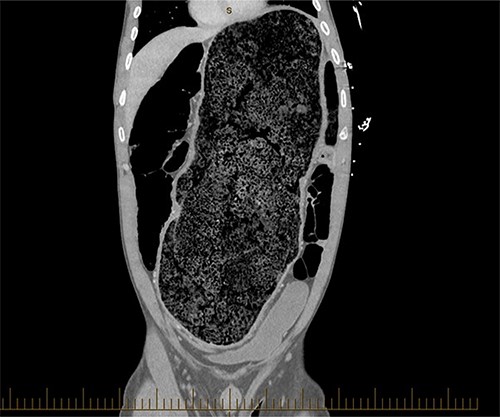

A 28-year-old gentleman self-presented to the emergency department with profuse overflow diarrhea and vomiting. The patient reported he had normal bowel motion until the morning of presentation. He denied any abdominal pain. On examination, the patient appeared pale, diaphoretic and dehydrated. His abdomen was grossly distended, however, was nontender. He was afebrile yet experienced sustained sinus tachycardia to a rate of 120 beats per minute. His blood pressure sat at 96/75 mmHg and was tachypneic to a respiratory rate of 30 and was saturating at 96% on room air. His blood tests showed a leukocytosis to 31, severe metabolic acidosis pH 7.18, lactate 7.7 and hyperkalemia K 6.0 estimated glomerular filtration rate (eGFR) of 68 mL/min/1.73 m2 and a creatinine count of 125μmol/L The computed tomography imaging of his abdomen revealed a massively dilated rectum and sigmoid colon extending to his splenic flexure without evidence of a perforation (Figs 1 and 2). Plain film radiography shows a sizeable faecaloma in the sigmoid colon (Fig. 3).

Coronal view of a CT image of a large faecaloma in the sigmoid.